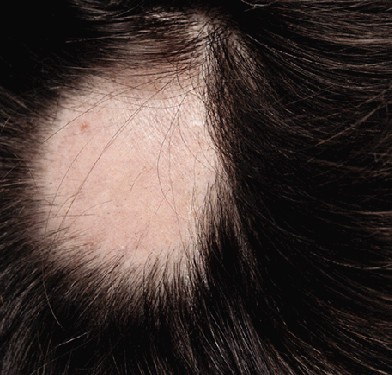

FOAIA DE OBSERVATIE CLINICA - Examenul obiectiv Semiologia fanerelor

FOAIA DE OBSERVATIE CLINICA - Examenul obiectiv Semiologia fanerelor q Semiologia parului Examinarea trebuie efectuata sistematic, cu minutiozitate, elemente aparent nesemnifiCiteste tot ... 2388 cuvinte

Dimensiune medie

+ cu poze |